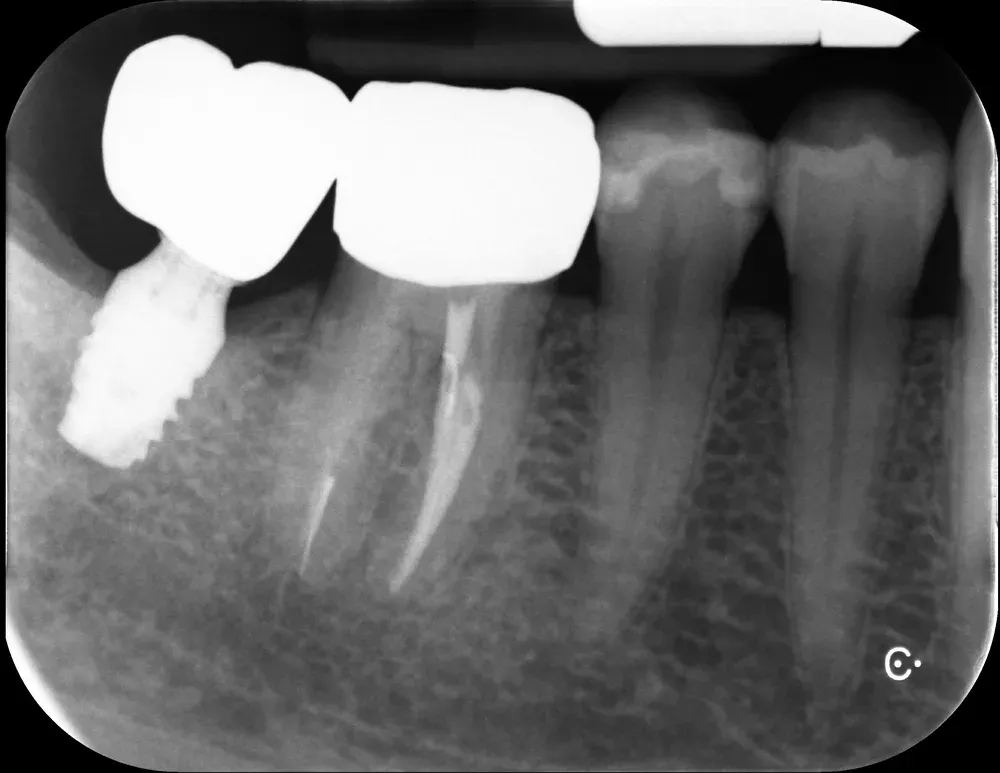

Gli impianti transmucosi devono essere posizionati transmucosi, soprattutto se hanno connessioni non particolarmente “sigillanti”. Usati in tal guisa, sono perfetti. Le immagini che seguono dimostrano che i transmucosi, se posizionati al giusto livello verticale, causano ZERO riassorbimento della cresta ossea.

La regola dei 4mm di Linkevičius ci viene in aiuto per stabilire la posizione verticale che protegge l’impianto dal riassorbimento osseo, sempre nel caso di connessioni affidabili dal punto di vista batteriologico. Nelle prossime immagini, dei monconi protesici relativamente lunghi su impianti a connessione conica, testimoniano l’ottimo risultato reale di questo concetto, con impianti perfettamente integrati e privi di infiltrazione infiammatoria, anche in condizioni ossee impegnative.

Per concludere il confronto tra le varie connessioni, l’immagine che segue è una radiografia con due impianti affiancati: un tissue-level ben posizionato fatto da un collega anni addietro e un impianto a connessione conica in posizione infracrestale con abutment della corretta lunghezza per il caso. Il secondo è un mio caso. È interessante notare come il cono dello spazio biologico sia identico. Se ben posizionati, tutti gli impianti funzionano egregiamente (l’impianto più vecchio inizia a soffrire un pochino, ma questa è un’altra storia).